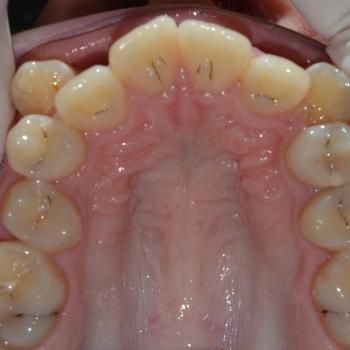

Közös döntés eredményeként fém önligírozó fogszabályozót választottunk, illetve a felső kisőrlők, illetve egy darab alsó metszőfog eltávolítására került sor. Az alsó metszőfog eltávolítása elsőre szokatlannak tűnhet, de a fogszabályozásban ez bevett gyakorlat hiszen esztétikai problémát nem okoz és a húzás által biztosított plusz hely rögtön a megfelelő helyen áll a rendelkezésünkre.

A kezelés befejeztével minden felmerülő problémát és eltérést sikerült megoldanunk, így egy funkcionálisan és esztétikailag is szép eredményt kaptunk.